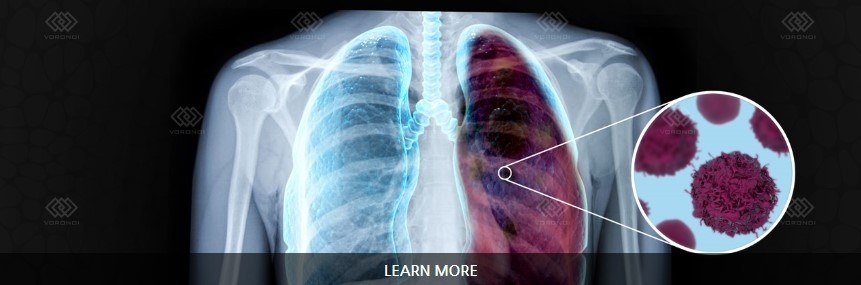

오늘은 단순한 감기와는 달리, 폐에 염증이 생기는 심각한 질환인 폐렴의 증상에 대해 이야기하려 합니다. 폐렴은 세균, 바이러스, 곰팡이 등 다양한 원인에 의해 발생하며, 특히 면역력이 약한 어린이나 노인에게 치명적일 수 있습니다.

- 호흡 곤란 및 가슴 통증

- 설명: 폐렴의 가장 심각하고 중요한 증상입니다. 폐에 염증이 생겨 폐 기능이 떨어지면서 숨쉬기 힘들어지며, 얕고 빠른 호흡을 하게 됩니다. 심한 경우 가슴에 통증을 느끼거나, 옆구리가 결리는 듯한 느낌을 받을 수 있습니다.